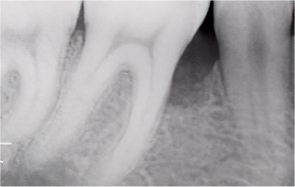

What is Periodontal Disease?

Periodontitis — commonly known as gum disease — is one of the most prevalent conditions

that destroys the gingiva and alveolar bone.

It begins with simple gum swelling

and bleeding,

but if left untreated, the alveolar bone gradually resorbs,

ultimately leading to tooth extraction.